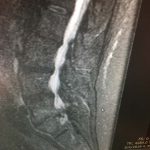

Μαγνητική τομογραφία:

Ανάλογα ευρήματα υπάρχουν και στην μαγνητική τομογραφία. Επί πλέον δε παρατηρείται:

- Εκφύλιση του μεσοσπονδύλιου δίσκου στο επίπεδο Ο3 – Ο4, περιορισμός του εύρους του σπονδυλικού σωλήνα και των μεσοσπονδύλιων τρημάτων, με πιεστικά φαινόμενα επί των Ο3 ριζών.

- Μικρού βαθμού εκφυλιστική σπονδυλολίσθηση στο επίπεδο Ο4 – Ο5, όπως και ιεροποίηση του 5ου οσφυϊκού σπονδύλου με πιεστικά φαινόμενα επί των συστοίχων νωτιαίων ριζών.

- Σαφής εκφύλιση του μεσοσπονδύλιου δίσκου Ο5 – Ι1 και στένωση του αναφερόμενου μεσοσπονδύλιου διαστήματος.

Εικόνα α,β,: Οβελιαίες λήψεις